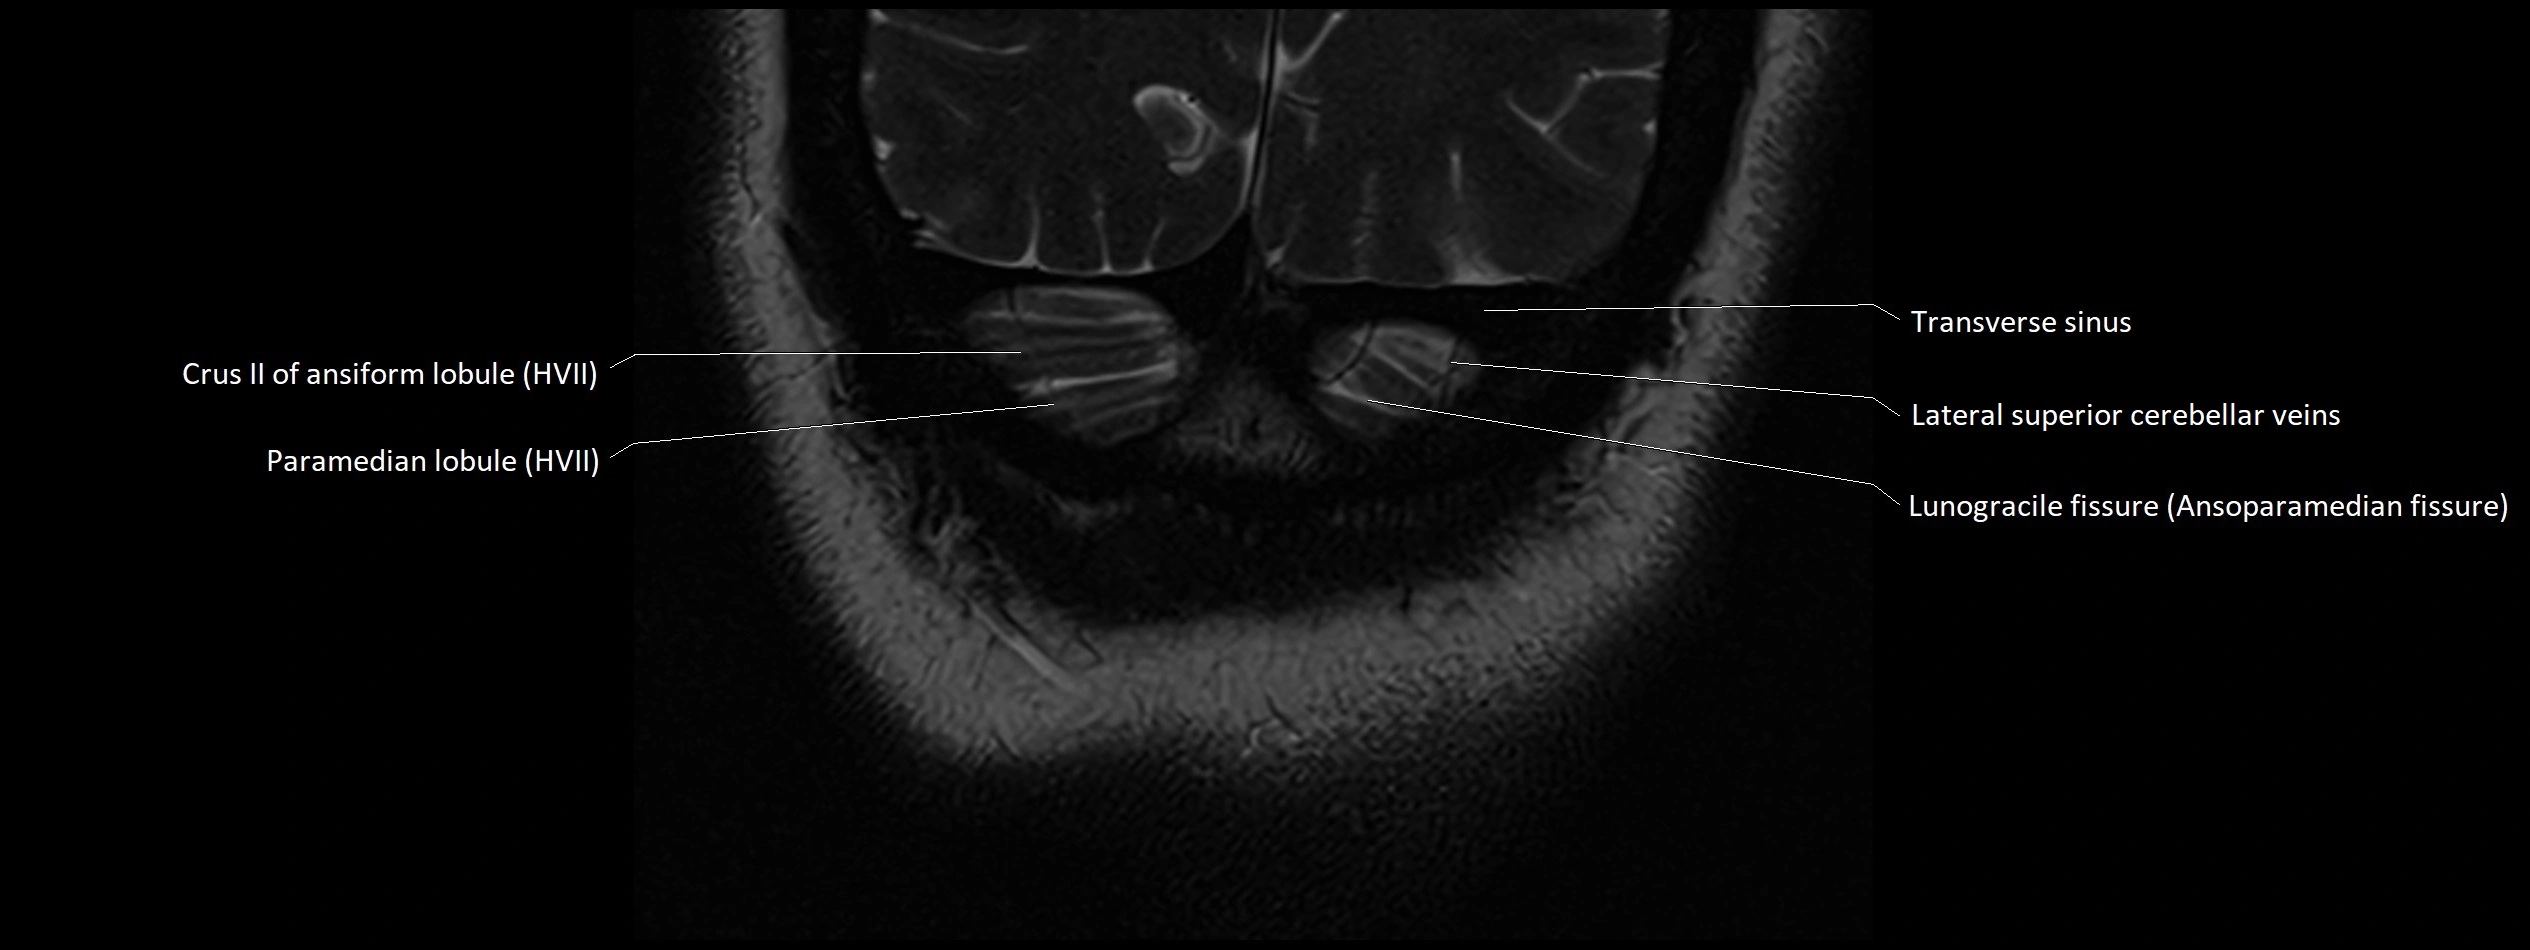

- Crus II of ansiform lobule of cerebellum

- Lunogracle fissure

- Lunogranicile fissure of cerebellum

- Paramedian lobule

- Paramedian lobule (HVII) of cerebellum

- Transverse sinus